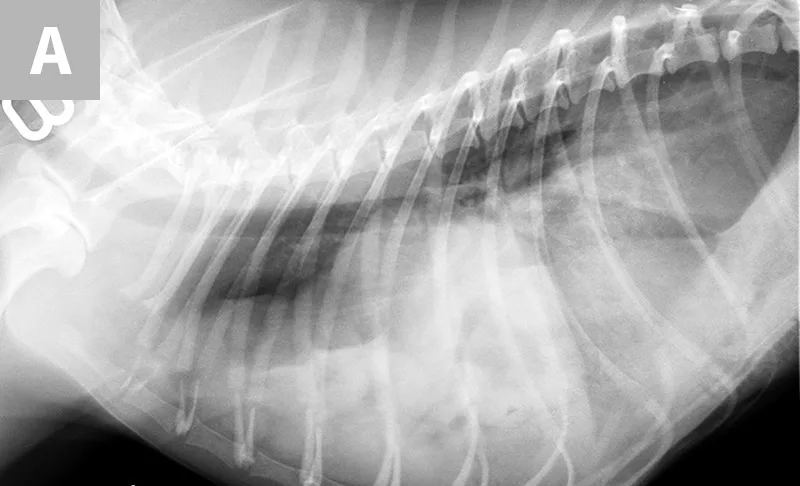

FIGURE 1A

Diaphragmatic hernia involving herniated liver, small intestine, colon, spleen, and mesentery in a 6-year-old spayed domestic shorthair cat.

Diaphragmatic hernia (Figures 1 and 2) has been categorized as acute (<14 days) or chronic (≥14 days) in the literature.2-4 In acute cases, initial stabilization of the patient and recognition of other underlying injuries are crucial. Higher mortality rates have been documented in animals with concurrent soft tissue injuries or in those with both soft tissue and orthopedic injuries.2